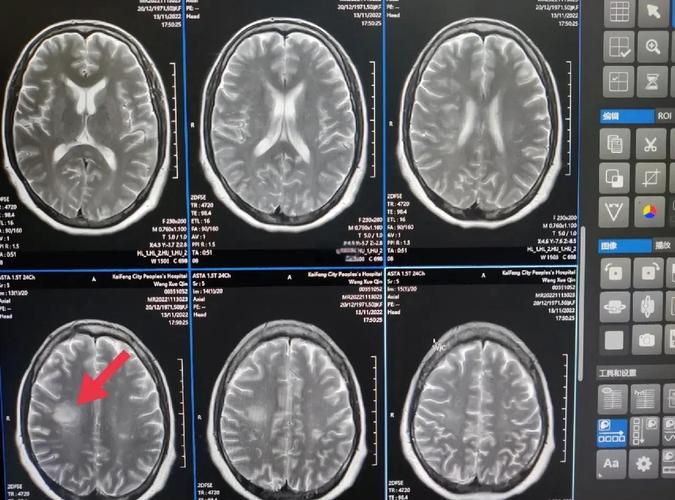

- 影像表现:在DWI图像上,新梗死的区域会显示为明显的高信号(亮白色),在另一个叫做“表观弥散系数”(ADC)的序列上,同一个区域会显示为低信号(暗黑色),这种“DWI高信号,ADC低信号”的组合是诊断急性期(通常指6小时内到2周内)脑梗死的“金标准”。

- 影像表现:在DWI和ADC序列上,陈旧梗死的区域通常没有上述的信号异常,它可能表现为一个与脑脊液信号相似的、边界清晰的低信号区(在T2序列和FLAIR序列上更明显),周围可能有胶质增生形成的信号改变。

DWI就像是脑梗死的“时间探测器”,能精准地捕捉到刚刚发生的脑细胞损伤。